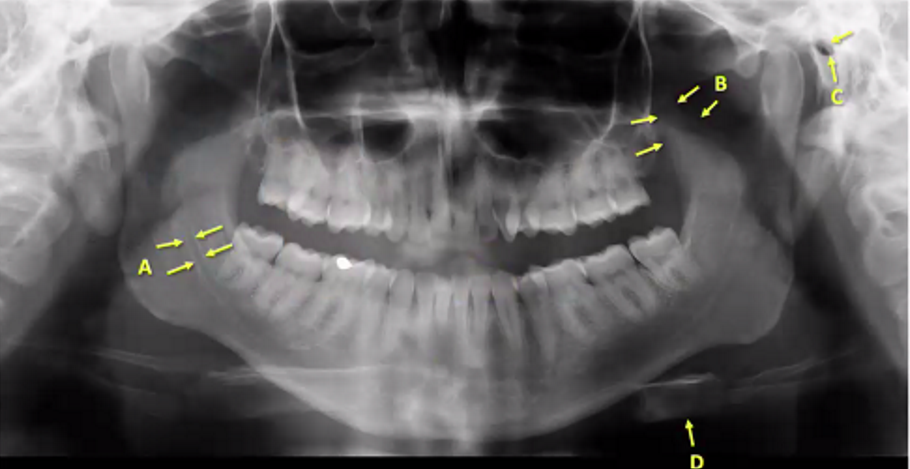

A

inferior alveolar canal (right)

B

left coronoid process

C

left external auditory meatus

D

left hyoid bone